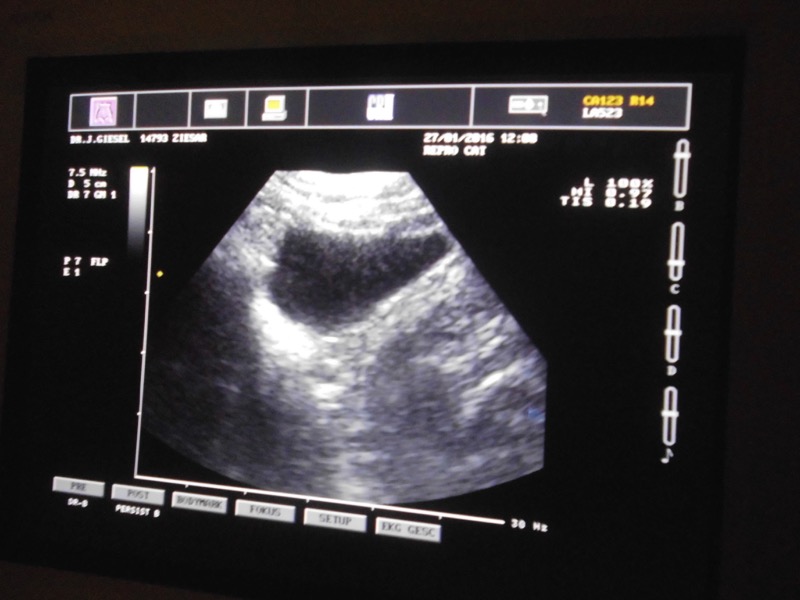

Eine Untersuchung mit Ultraschall ist ohne Narkose möglich und völlig schmerzfrei. Etwas stressig ist die Prozedur natürlich trotzdem für die Tiere - aber es ging alles sehr zügig und ist immer noch besser, als sich unerkannt krank im Gehege zu quälen. Viele Menschen wissen aus eigener Erfahrung um die schlimmen Schmerzen von Harnsteinen. Deshalb kann man auch privaten Tierhaltern nur empfehlen, ab und zu einen Tierarzt prüfen zu lassen.

Unsere Tiere waren alle ohne Befund. Ein Meerschweinchen musste zur genauen Abklärung noch geröntgt werden. So sind wir nun erst einmal wieder beruhigt.